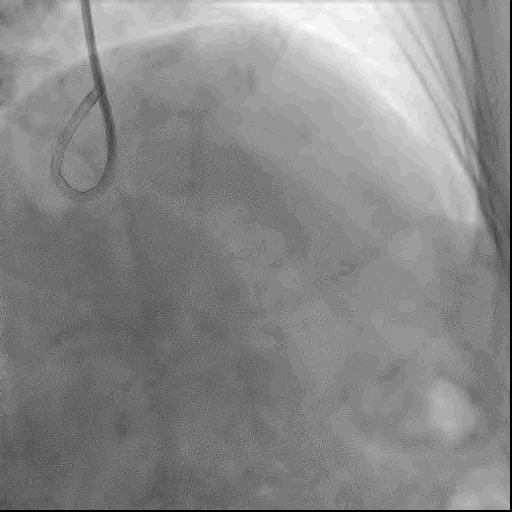

手术策略:左冠冠脉造影示LM中远段狭窄60%,累及LCX开口狭窄75%;LAD发出D1后齐头闭塞,无残端,远端微小侧支循环形成,显影差。患者逆向侧支循环显影差,故选择正向策略。

首先送入双腔微导管,依次尝试使用XTR导丝、UB3导丝、Gaia3导丝后成功通过闭塞段,影像学反复定位确定导丝位于血管真腔内。后更换为Cosair微导管并送入UB3导丝,通过闭塞段到LAD远端。

● 术前冠脉造影提示LAD齐头闭塞,无残端,逆向的侧支循环显影也较差,故逆向策略暂不考虑,首选前向策略。术者通过反复更换导丝及导丝升级成功通过LAD闭塞段。